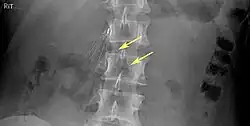

Of these IVC filter side effects, 328 involved device migration, 146 involved embolizations after detachment of device components, 70 involved perforation of the IVC, and 56 involved filter fracture. Much of the medical community believes that this large number of adverse events is related to the heart filter remaining in place for longer than necessary.

Common issues relating to failure, to include death (the other 4% of cases) include:

- Filter fracture

- 9% (12 of 132 patients) delayed filter penetration of the IVC greater than 3 mm

- Parts of filter broke off in 2% (5 of 230 patients)

- Filter fracture: Broken struts migrate to retroperitoneum, requiring exploration.[21] Also struts can migrate to the heart and can cause pericardial effusion and tamponade.[22]